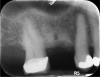

In this case, the patient’s right maxillary first molar had been extracted, and the site was grafted. The periapical radiograph taken after 6 months of healing indicated the presence of dense bone (Figure 11). There was also ample attached mucosa (Figure 12). Impressions were taken, a diagnostic cast was made, and a wax-up of the restoration was placed in the model (Figure 13). To make the radiographic guide for this case, a silicone putty index was created over the diagnostic wax-up, as described earlier. A panoramic radiograph and a CBCT scan (Figure 14) were taken with the radiographic guide in place; the guide post in the index can clearly be seen.

Fig 11. Site No. 3, 6 months after extraction and bone grafting completed.

Figure 11